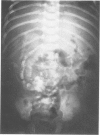

Fetus-in-fetu is an unusual cause of retroperitoneal abdominal mass in infants, which most likely arises from inclusion of a monozygotic, diamniotic twin. This entity is distinguished from teratoma by its embryological origin, its unusual location in the retroperitoneal space, its invariable benignity, and by the presence of vertebral organization with limb buds and well-developed organ systems. Diagnosis is made radiographically by the finding of a diminutive vertebral column on a plain abdominal film. The treatment of choice is total excision with special attention being given to the fetus' blood supply which may be directly from the host's superior mesenteric vessels. A well-documented example of this unusual entity that occurred in a six-week old infant male is presented.